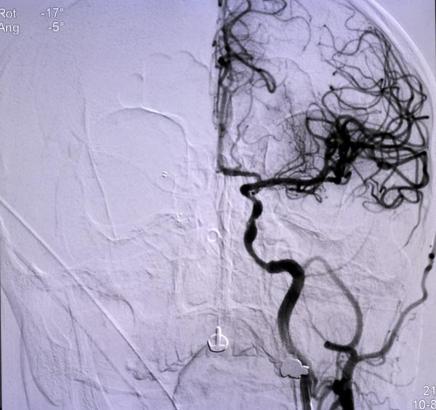

Niğde’den ellerinde uyuşma şikayeti sonrası başvurduğu hastaneden Konya’ya sevk edilen Ömer Altan’ın (73), kısa sürede müdahalesi yapılarak, tıkanan ana damarını açtıklarını belirten Doç. Dr. Gökhan Özdemir, “Hastamız Niğde şehrinden bize başvurdu. Oradaki hekim arkadaş hastayı değerlendirdi. Beyni besleyen ana büyük damarında ciddi bir darlığı tespit etti. Bu da hastanın felç geçirmesine sebep olan bir durum. Oradaki doktor arkadaş hızlıca bize ulaştı ve biz de hastayı kabul ettik. Bekletmeden burada hastanın müdahalesini yaptık, ana damarını açtık. Ana damar olduğundan dolayı bu hastaların büyük bir kısmı ölüyor. Yani beyni besleyen ana büyük damarlardan biri tıkandığı zaman genelde bu hastanın yüzde 50-60’ı ölüyor. Ölmese bile büyük ihtimalle ömür boyu özürlü kalacaktı” dedi. (DHA)